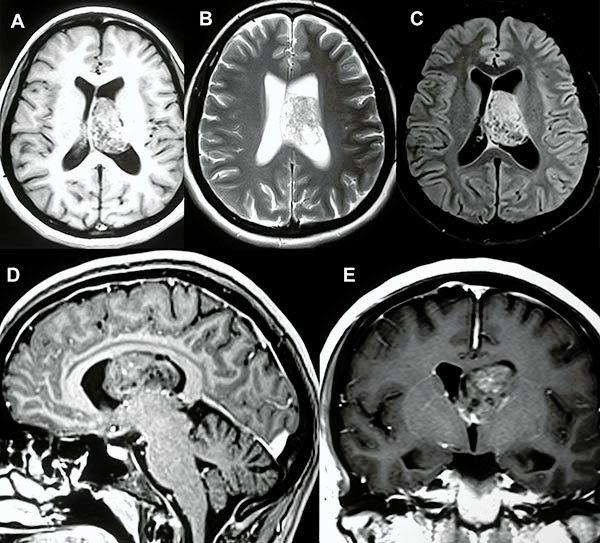

En el estudio de resonancia magnética del encéfalo se observó lesión redondeada, intraventricular a nivel de ventrículo lateral izquierdo, de bordes netos, de aproximadamente 40x30x30 mm, de señal heterogénea, predominantemente isointensa respecto a sustancia gris en T1 con presencia de focos de baja señal en su interior. En T2 se observa lesión predominantemente hiperintensa, múltiples imágenes de aspecto quístico en su interior (aspecto de burbujas) que en el FLAIR dichas imágenes quísticas son atenuadas. Tras la administración de contraste endovenoso se observa moderada y heterogénea captación del mismo (fig. 1).

Figura 1:

A, B y C) Cortes axiales en las secuencias ponderadas en T1, T2 y FLAIR respectivamente. D) Corte sagital de secuencia ponderada en T1 con contraste. E) Corte coronal de secuencia ponderada en T1 con contraste.